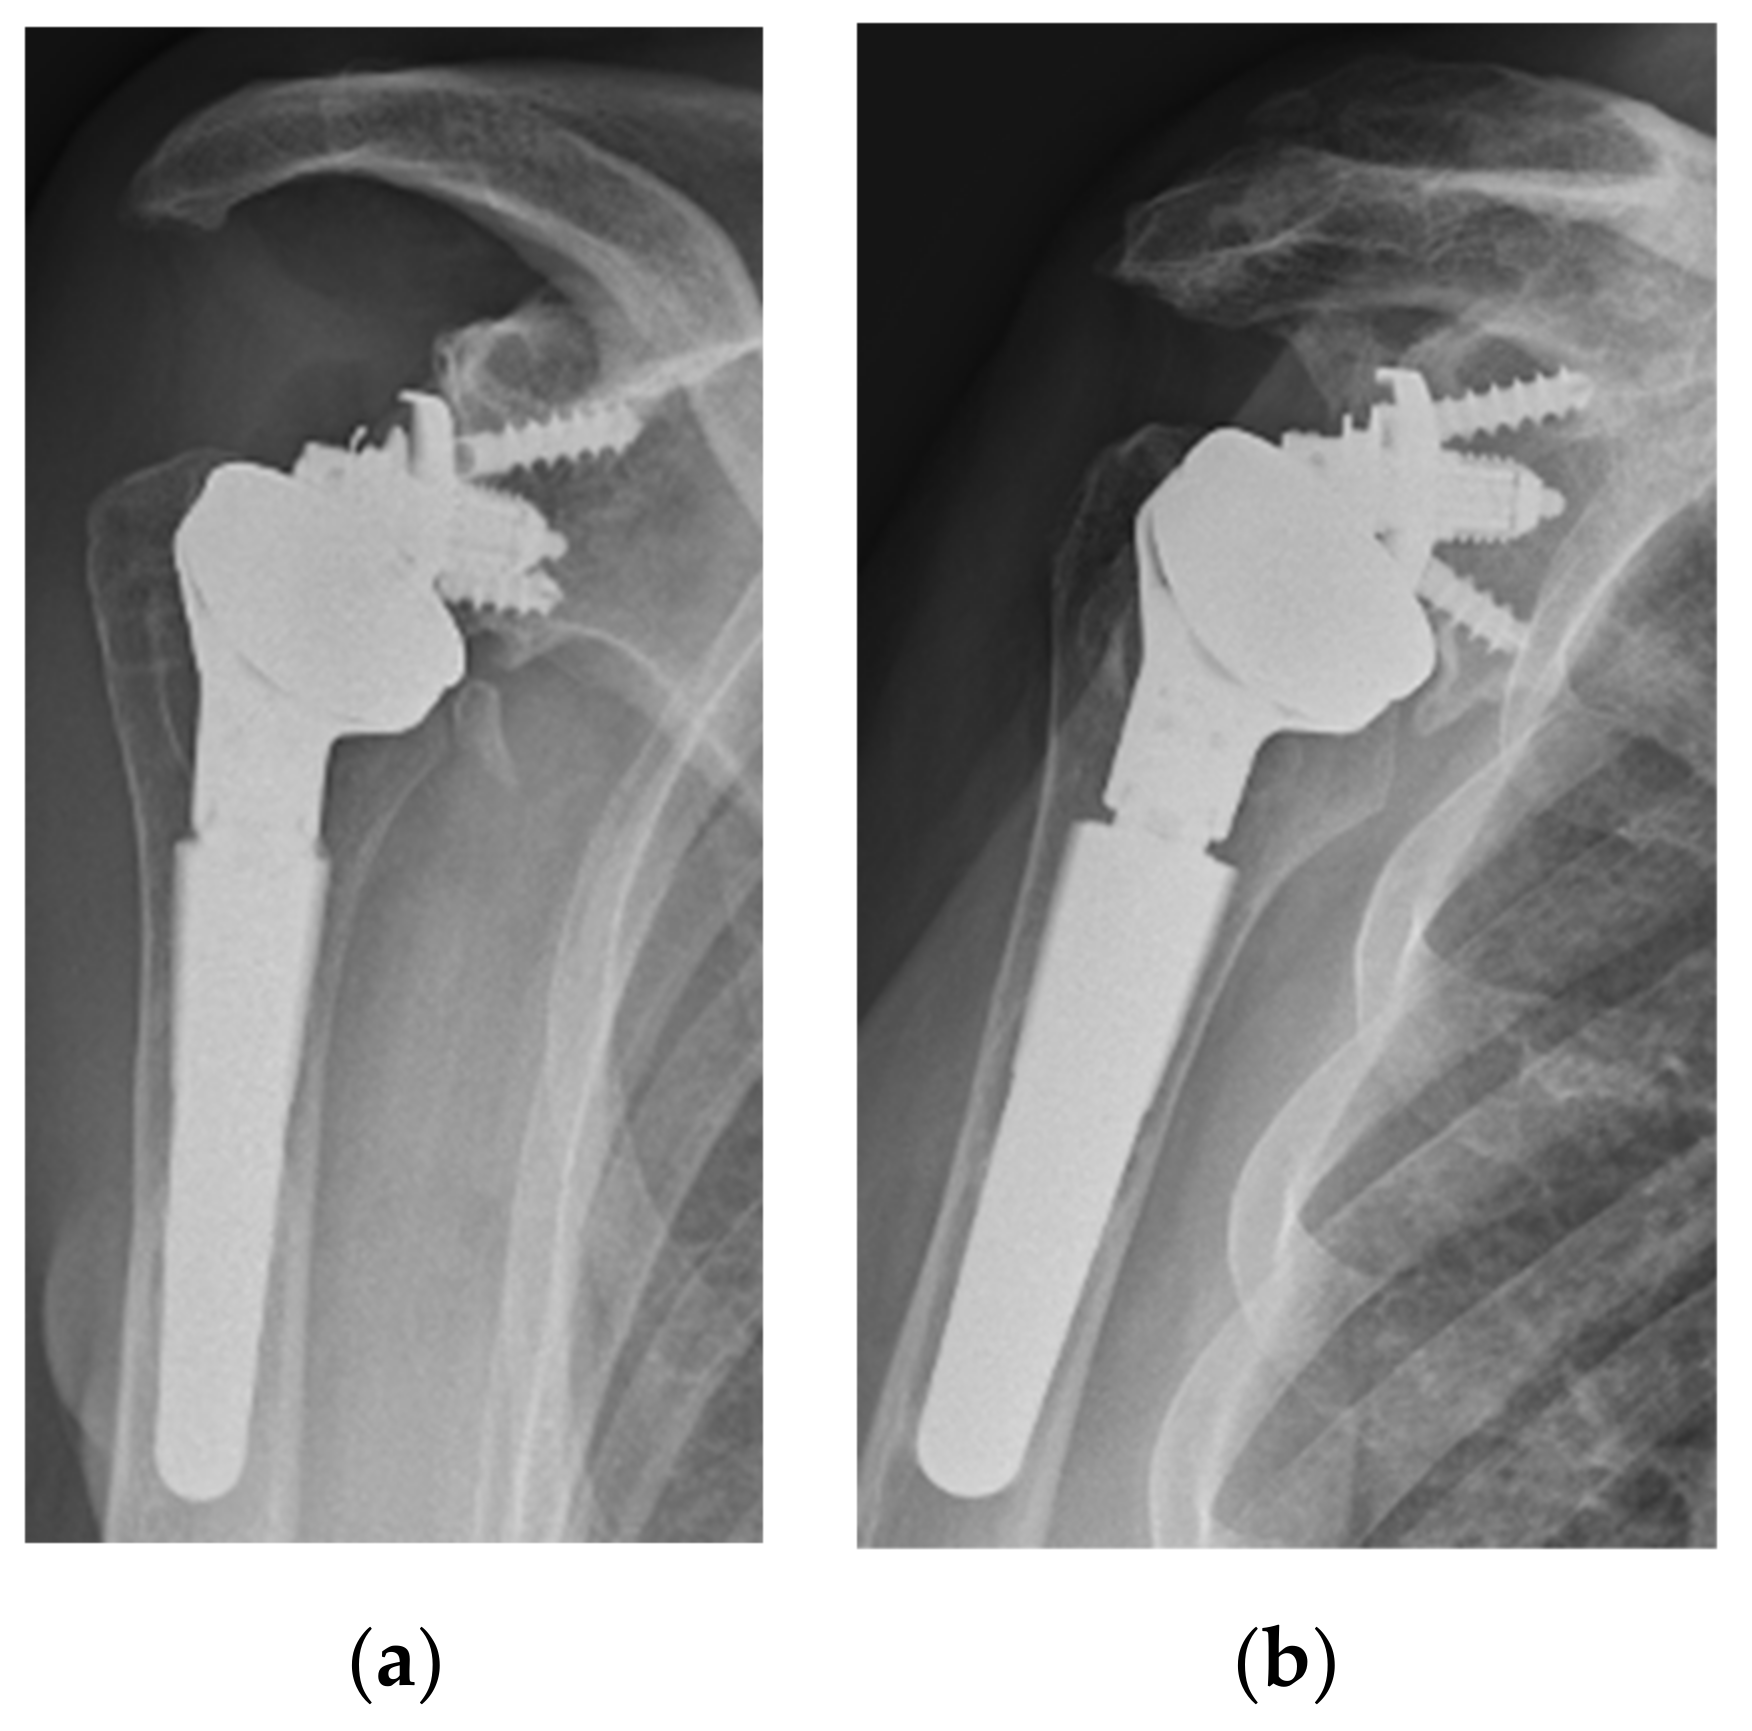

Scapular notching remain the most common complication associated with RSA [1,3]. In this series, notching occurred in 27% cases. Even though this rate still is not completely satisfying, it is lower compared to the notching rates (40–68%) of similar standard bearing RSA with a classic Grammont humeral stem with or without a lateralized glenoid [1,8,15,16,25]. Moreover, it must be underlined that the notching observed in this series has peculiar features. First, at this follow-up, no grade higher than 2 was observed (Figure 5).

As postulated by Friedman et al., grade 3 and 4 extending over the inferior screw are likely the results of a biologic response to polyethylene particles and osteolysis [3]. Secondly, in all cases with notching, a bone spur on the scapular neck was present. Third, the notching was almost only present in cases with a high position of the baseplate, a condition that is proven to be associated with mechanical contact of the prosthesis with the scapula [5,8,11,26]. All these features seem to be linked to a pure mechanical notching, proving that IB-RSA with a hard humeral liner leads to a distinct type of scapular notching and avoids PE wear-induced osteolysis at mid-term follow-up. Similar findings were shown by Kohut et al. using a different IB-RSA [27]. Based on our findings, optimal (as low as possible) and secure (optimal preparation of the subchondral bone) positioning of the glenoid is mandatory to avoid scapular notching (Figure 6).

Figure 5. Two cases with a high glenoid position that developed a grade 1 (a) and grade 2 (b) of notching with the formation of a bone spur.